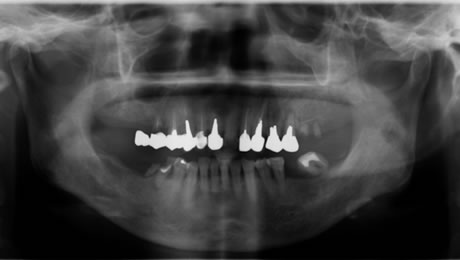

下のレントゲンと口腔内写真は先日インプラント治療が終わった患者さんの初診時です。

いままで仕事が忙しく、口内清掃が不良で歯が喪失していました。

仕事をリタイヤし、これからの人生を快適に過ごすため口腔内をしっかり治したいので来院されました。

歯石の沈着、プラークコントロール不良で、歯肉の発赤がみられます。

奥歯は歯周病、虫歯を放置していたため歯が喪失しています。 |